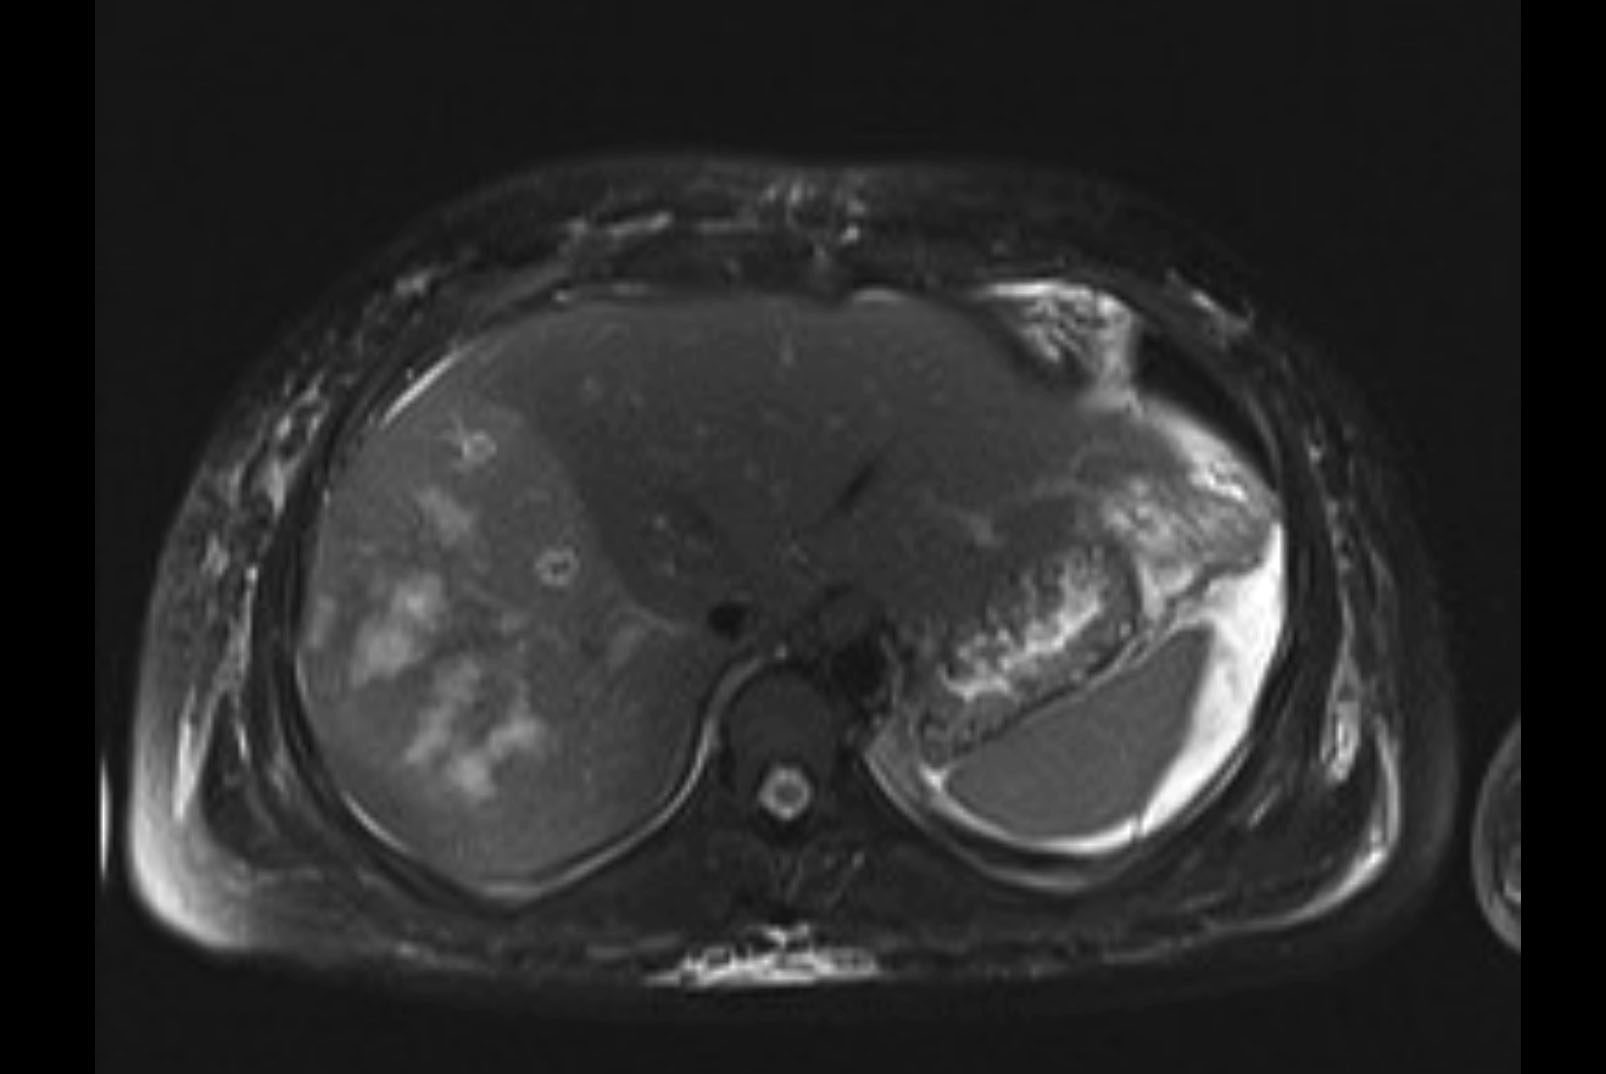

MRI T1

MRI T2

Imaging analysis

Based on initial findings, which issue(s) would you be most concerned about?